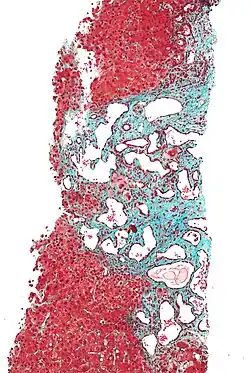

| Histopathology of a bile duct hamartoma, low magnification, H&E stain, showing a well demarcated lesion. |